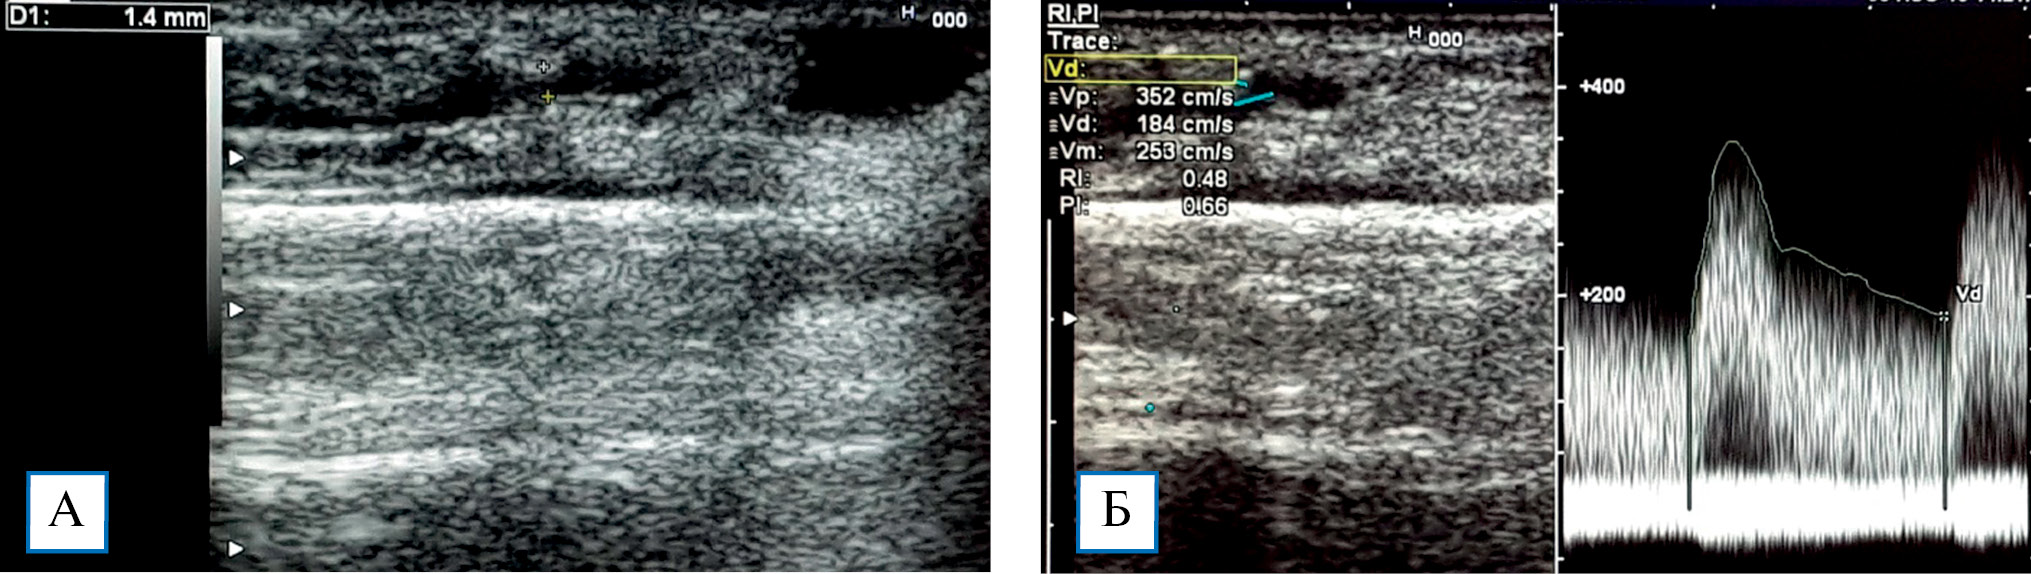

Ультразвуковое исследование позволило выявить основные причины развития стил-синдрома: стенозы приводящей артерии у пациентов с атеросклерозом и сахарным диабетом (рис. 1), которые не позволяют увеличить объемный кровоток в артерии (у 3; 20,0%); большой диаметр анастомоза, обусловливающий значительное шунтирование крови (рис. 2), дилатацию вены и повышение ОСК (у 2; 13,3%); недостаточный приток крови по локтевой, передней межкостной артериям и отсутствие коллатеральных ветвей, которые не компенсировали ретроградный кровоток из лучевой артерии дистальнее анастомоза в фистулу (у 6; 40,0%); нарушение механизмов регуляции тонуса резистивных сосудов и патологические изменения микроциркуляторного русла кисти (у 4; 26,7%). Неполный вариант строения пальмарных дуг предрасполагает к развитию синдрома обкрадывания кисти.

Рис. 1. Эхограммы гемодинамически значимого стеноза приводящей (лучевой) артерии: диаметр свободного просвета лучевой артерии в зоне стеноза 1,4 мм (А); ускорение пиковой систолической скорости кровотока в области стеноза до 352 см/с, что свидетельствует о стенозе 80–90% (Б)